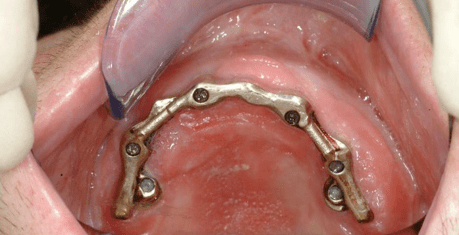

Den vorbereitenden Operationen wie Ausformung der Weichgewebe und weiterer Knochenaufbau folgte 2001 das Einbringen von insgesamt 11 Implantaten, die – jeweils in Ober- und Unterkiefer über eine spezielle Konstruktion verbunden – die Zahnprothesen tragen.